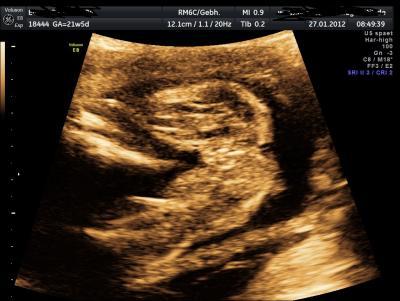

Bin gespannt was ihr so seht oder eben nicht

Bild zu Was meint Ihr? - Forum für Juni - Mamis

das ist der popo von unten fotografiert. ;-) die längeren teile sind die Oberschenkel und dazwischen ist halt der Schritt entweder mit schniepel oder eben ohne wie hier ;-)

Laut Arzt von der Pränataldiagnostik ein Mädchen und meine Fa vermutete letztens auch ein Mädchen, aber die Beinchen lagen etwas im Weg